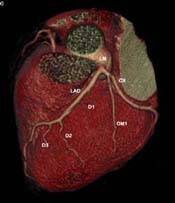

Cardiac

CT |

Why is it

called Ultra-Fast CT?

A regular CT has tube rotation speed of 1 or .75 seconds.

This CT has tube rotation speed of 330ms, i.e. approximately

3 rotations per second. This allows extremely fast

scans of the body, such that routine chest and abdomen

sequences can be completed in 3-5 seconds. That is

why it is called Ultra-Fast CT.

How does cardiac CT work?

With such a fast scanner, it is possible to "freeze"

the heart. The new 64-slice scanner obtains almost

194 slices per second. After gating with the ECG,

it is possible to scan the heart in 10-12 seconds

and to extract information about the coronary arteries

and cardiac function from the dataset.